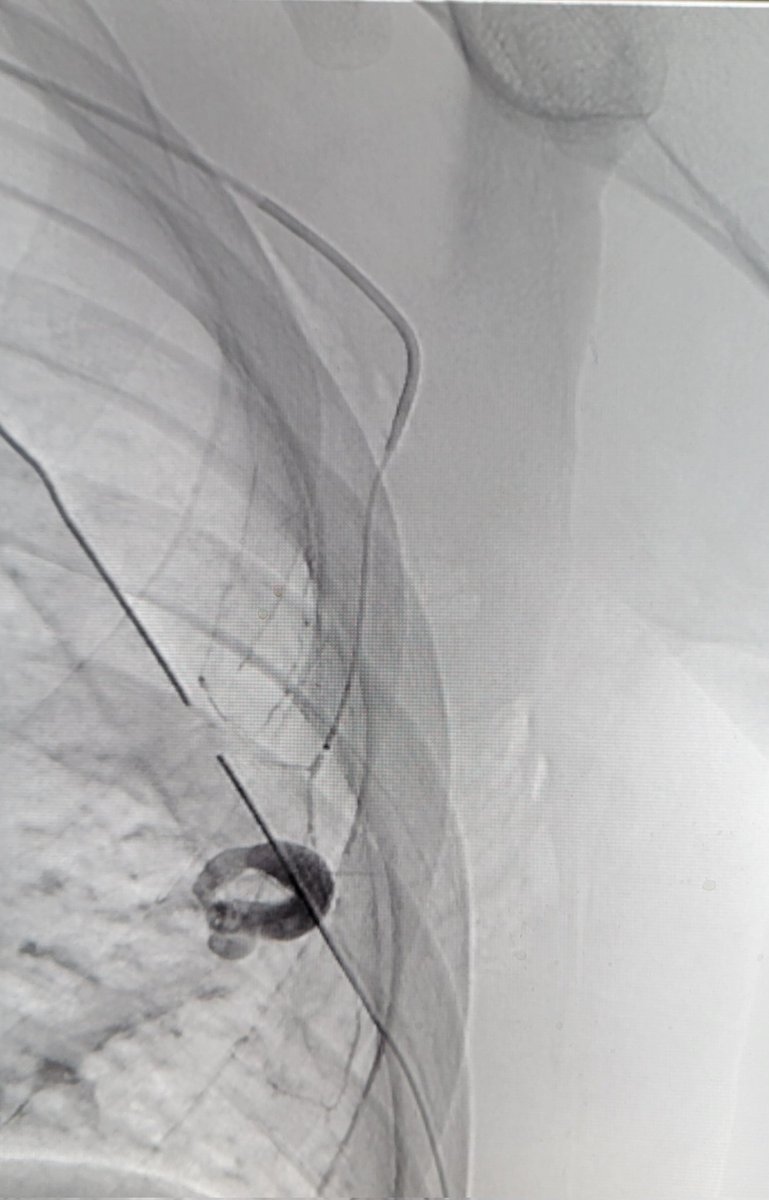

Patient w/ stab wound to chest. CT shows large hematoma with active bleed. Initial angio of intercostals and int mammary was neg. Finally, bleed found off lateral thoracic. Nice hunting Dr. Derek Lee @IanSLeopold! Great read @BlachyDavila Dr. Graf @TempleRadRes @templechestrads